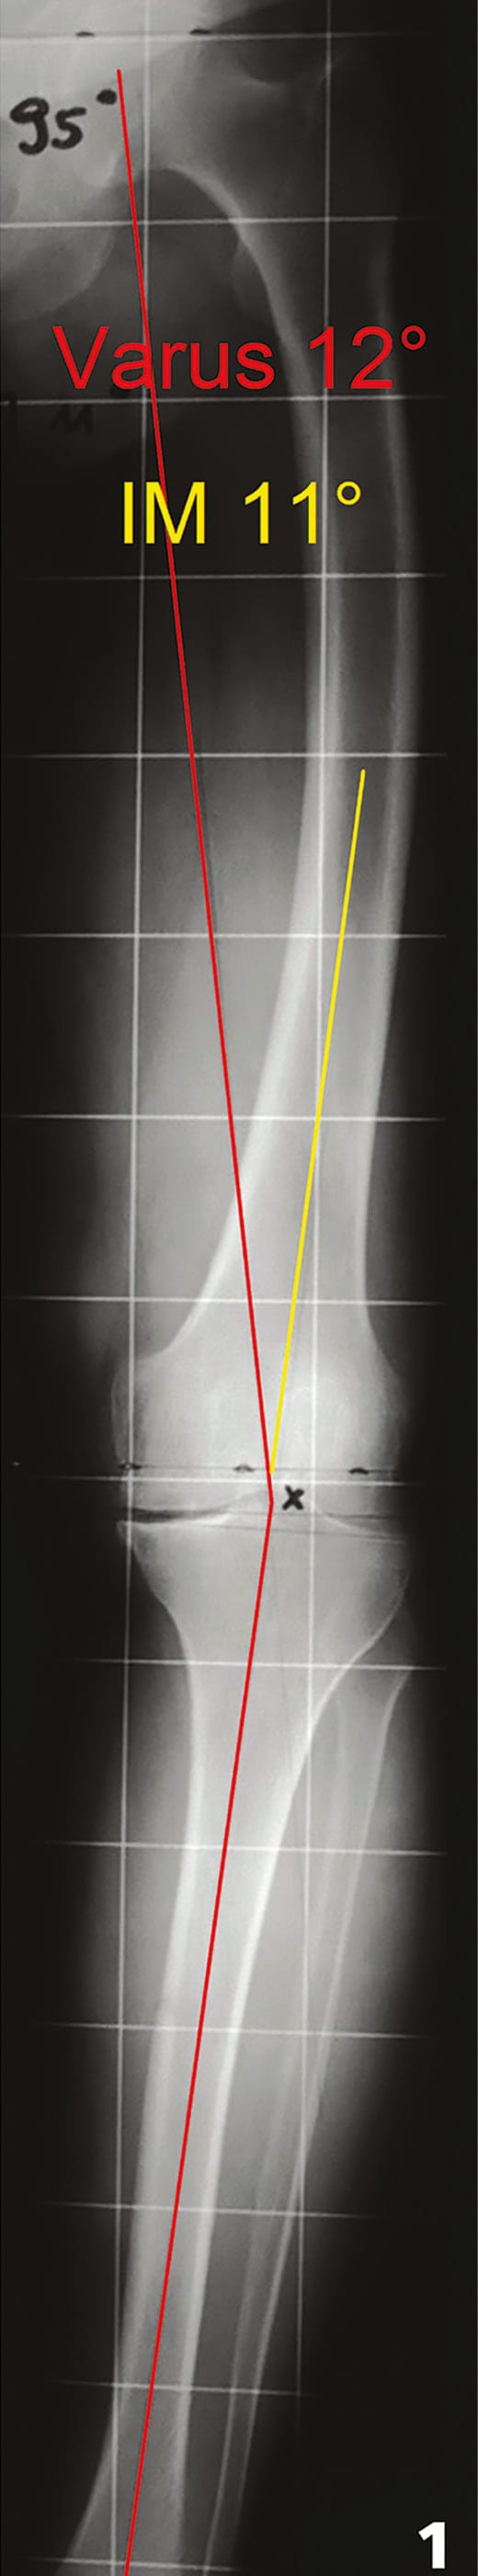

Standard anterior-posterior weight bearing and lateral non-weight bearing radiographs were used to estimate the severity of arthritis, osteophytes and bony defects. Templating the size of the implants was performed in exceptional cases only. A standardized frontal full leg weight bearing x-ray (Figure 1) was used for deformity analysis and planning of the intramedullary correction angle (IM-angle) at the femur [22] Pietsch M, Hofmann S (2006). Value of radiographic examination of the knee joint for the orthopedic surgeon (German). Radiologe 46: 55-64. In patients with clinical suspicion of patella maltracking a special weight bearing patella axial view was performed additional [10]Chauhan SK, Clark GW, Lloyd S, Scortt RG, Breidahl W, Sikorski JM (2004). Computer-assisted total knee replacement: A controlled Cadaver Study using a multi-parameter quantitative CT assessment of Alignment (The Perth CT Protocol) J Bone Joint Surg Br 86: 818-823.

The planning in the frontal plane was performed on the full leg x-ray and included deformity analysis according to Paley [21] Paley D, Herzenberg JE, Tetsworth K, McKie J, Bhave A (1994). Deformity planning for frontal and sagittal plane corrective osteotomies. Orthop Clin N Am 25: 425-465. The mechanical axis of femur, tibia and baselines of distal femur and proximal tibia are drawn on the radiograph (Figure 1 and 2). The varus or valgus malalignment, the mechanical distal lateral femur angle (LDFA - normal 88°, range 85-90) and mechanical medial proximal tibia angle (MPTA - normal 87°, range 85-90) were calculated (Figure 2). Furthermore the individual IM-angle between the mechanical and the anatomical axis of the femur was analyzed. With these four numbers the severity and location of the frontal bony deformity as well as the individual IM-angle could be identified before surgery. Depending on the necessary correction cuts for neutral alignment (LDFA and MPTA 90°), the need for additional soft tissue releases could be estimated also. In the case of figure 1 for example with a contract varus deformity of 12° the valgus correction cuts of 5 mm each on the femur and tibia (1° ~ 1mm) will end up with an further 10 mm increase in the trapezoidal extension gap. Together with the already contract medial soft tissue structures this will need extensive medial releases to correct this contract varus deformity.

Intraoperative controls before bone cuts

The frontal correction bone cuts were determined by the individual LDFA and MPTA only (Table 2). After using the conventional intramedullary instruments for preliminary placement at the femur, the cutting block position to the distal femur condyles was controlled by the LDFA as the “golden standard”. In the case of figure 1 for example the distal cutting block must be flush on the lateral condyle and has to show a 5 mm lift off on the medial side (1 mm ~ 1°) (Figure 3). This will guarantee a 5° valgus correction cut at the distal femur. If necessary the IM correction angle of the instrument was changed to adjust the cutting block positioning according to the LDFA. At the tibia the individual tibial intramedullary entry point was planned on the full leg x-ray and an intramedullary alignment with a combined extramedullary control rod was used for the frontal correction cuts in all cases except of 6 severe bowed tibias where an extra medullary system could be used only. The landmarks for the frontal extramedullary control were the anterior tibia crest, centre of the ankle (5 mm medial to the midline of both malleolus) and lateral to the tibialis anterior tendon. The second tarsal toe was not used due to lack of save forefoot torsion control. The placement of the cutting block was then double checked by the MPTA. In the case of figure 1 for example the proximal cutting block should cut 5 mm more lateral than medial to guarantee a 5° valgus correction cut.

For example in the case of figure 1 (the thickness of the distal metal of the NexGen LPS Flex Fixed® is 9 mm for all sizes) the lateral distal femur cut should be 9 and the medial 4 mm respectively (Figure 4). In varus deformities with varus femurs (the lateral condyle is the most distal contact point for the cutting block), the intact cartilage of the lateral distal condyle was taken into account. The same was done in a mirror wise fashion with valgus deformities and normal or valgus femurs.

Planning is a crucial part of a successful TKA and should include history, clinical examinations, radiographic analysis and planning on a weight bearing full leg length radiograph [22] Pietsch M, Hofmann S (2006). Value of radiographic examination of the knee joint for the orthopedic surgeon (German). Radiologe 46: 55-64. The standardized weight bearing full leg radiograph represent the key for deformity analyzes and planning of the long axis in the frontal plane (Figures 1 and 2). On short x-rays the tibiofemoral angle can be measured only, which does not allow analysis of the deformity and the mechanical axis of the whole leg. The overall mechanical axis, deformity analysis and IM-correction angle are necessary for proper frontal alignment correction [16], Hofmann S, Djahani O, Pietsch M (2007). Conventional navigation without computer and the lateral minimally invasive approach for contract valgus knee (German). Orthopäde 36: 1135-1142[22] Pietsch M, Hofmann S (2006). Value of radiographic examination of the knee joint for the orthopedic surgeon (German). Radiologe 46: 55-64.

With deformity analysis according to Paley [21] Paley D, Herzenberg JE, Tetsworth K, McKie J, Bhave A (1994). Deformity planning for frontal and sagittal plane corrective osteotomies. Orthop Clin N Am 25: 425-465 about half of the varus knees (48%) the bony deformity was located at the femur and the tibia was normal in this study (Figure 1). This means, that the lateral and not the medial condyle was the most distal part for the cutting block positioning at the femur. Additional in valgus knees 35% showed the deformity at the tibia only and in 47% it was located at tibia and femur. As we operate in almost all cases knees with deformities, the frontal distal femur and proximal tibia cuts are individual, depending on the location of deformity only and should be planned by deformity analyzes using LDFA and MPTA (see Table 2).